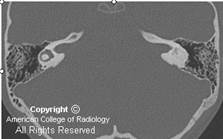

TAC: (Fig.16a-b-c)

Si consideri una tomografia computerizzata (CT) scansione prima della puntura lombare nei casi di possibile meningite. Una TAC è utile anche per aiutare a escludere mastoidite come causa potenziale. Un TAC dell’temporale osso può essere di aiuto nella gestione dei pazienti con colesteatoma e labirintite.

Una scansione TAC senza contrasto è migliore per la visualizzazione di fibrosi e calcificazione del labirinto membranoso in persone con labirintite cronica o ossificante labirintite.

Fig.16a Labirintite ossificante. Immagine coronale CT ottenuta in un altro paziente mostra anomala deposizione di osso nella coclea (freccia dritta) anteriore alla IAC, con un normale promontorio cocleare (freccia curva) prodotto dal giro basale della coclea. Queste caratteristiche sono visti in labirintite ossificante ma non in aplasia cocleare. |

![]() ![]() |

| Vi è l’obliterazione osseo della coclea visualizzate (Fig.16b), vestibolo, e il canale semicircolare laterale (Fig.16c). Diagnosi: labirintite ossificante Il fattore eziologico più comune è l’infiammazione dell’orecchio interno, secondaria a meningite batterica e la successiva purulento labirintite. Altre cause meno comuni includono labyrinthectomy, traumi dell’osso temporale, malattia autoimmune dell’orecchio interno, sequela di parotite o morbillo, e otite media con associato labirintite suppurativa. Ossificazione in labirintite ossificante comunemente si verifica principalmente al giro basale della coclea, che è l’inserimento sito degli elettrodi di dispositivi di impianto cocleare, e successivamente può interferire con l’inserimento completo e risultati di successo. MRI è utilizzato per valutare per la fibrosi precoce prima della formazione di calcificazione. |